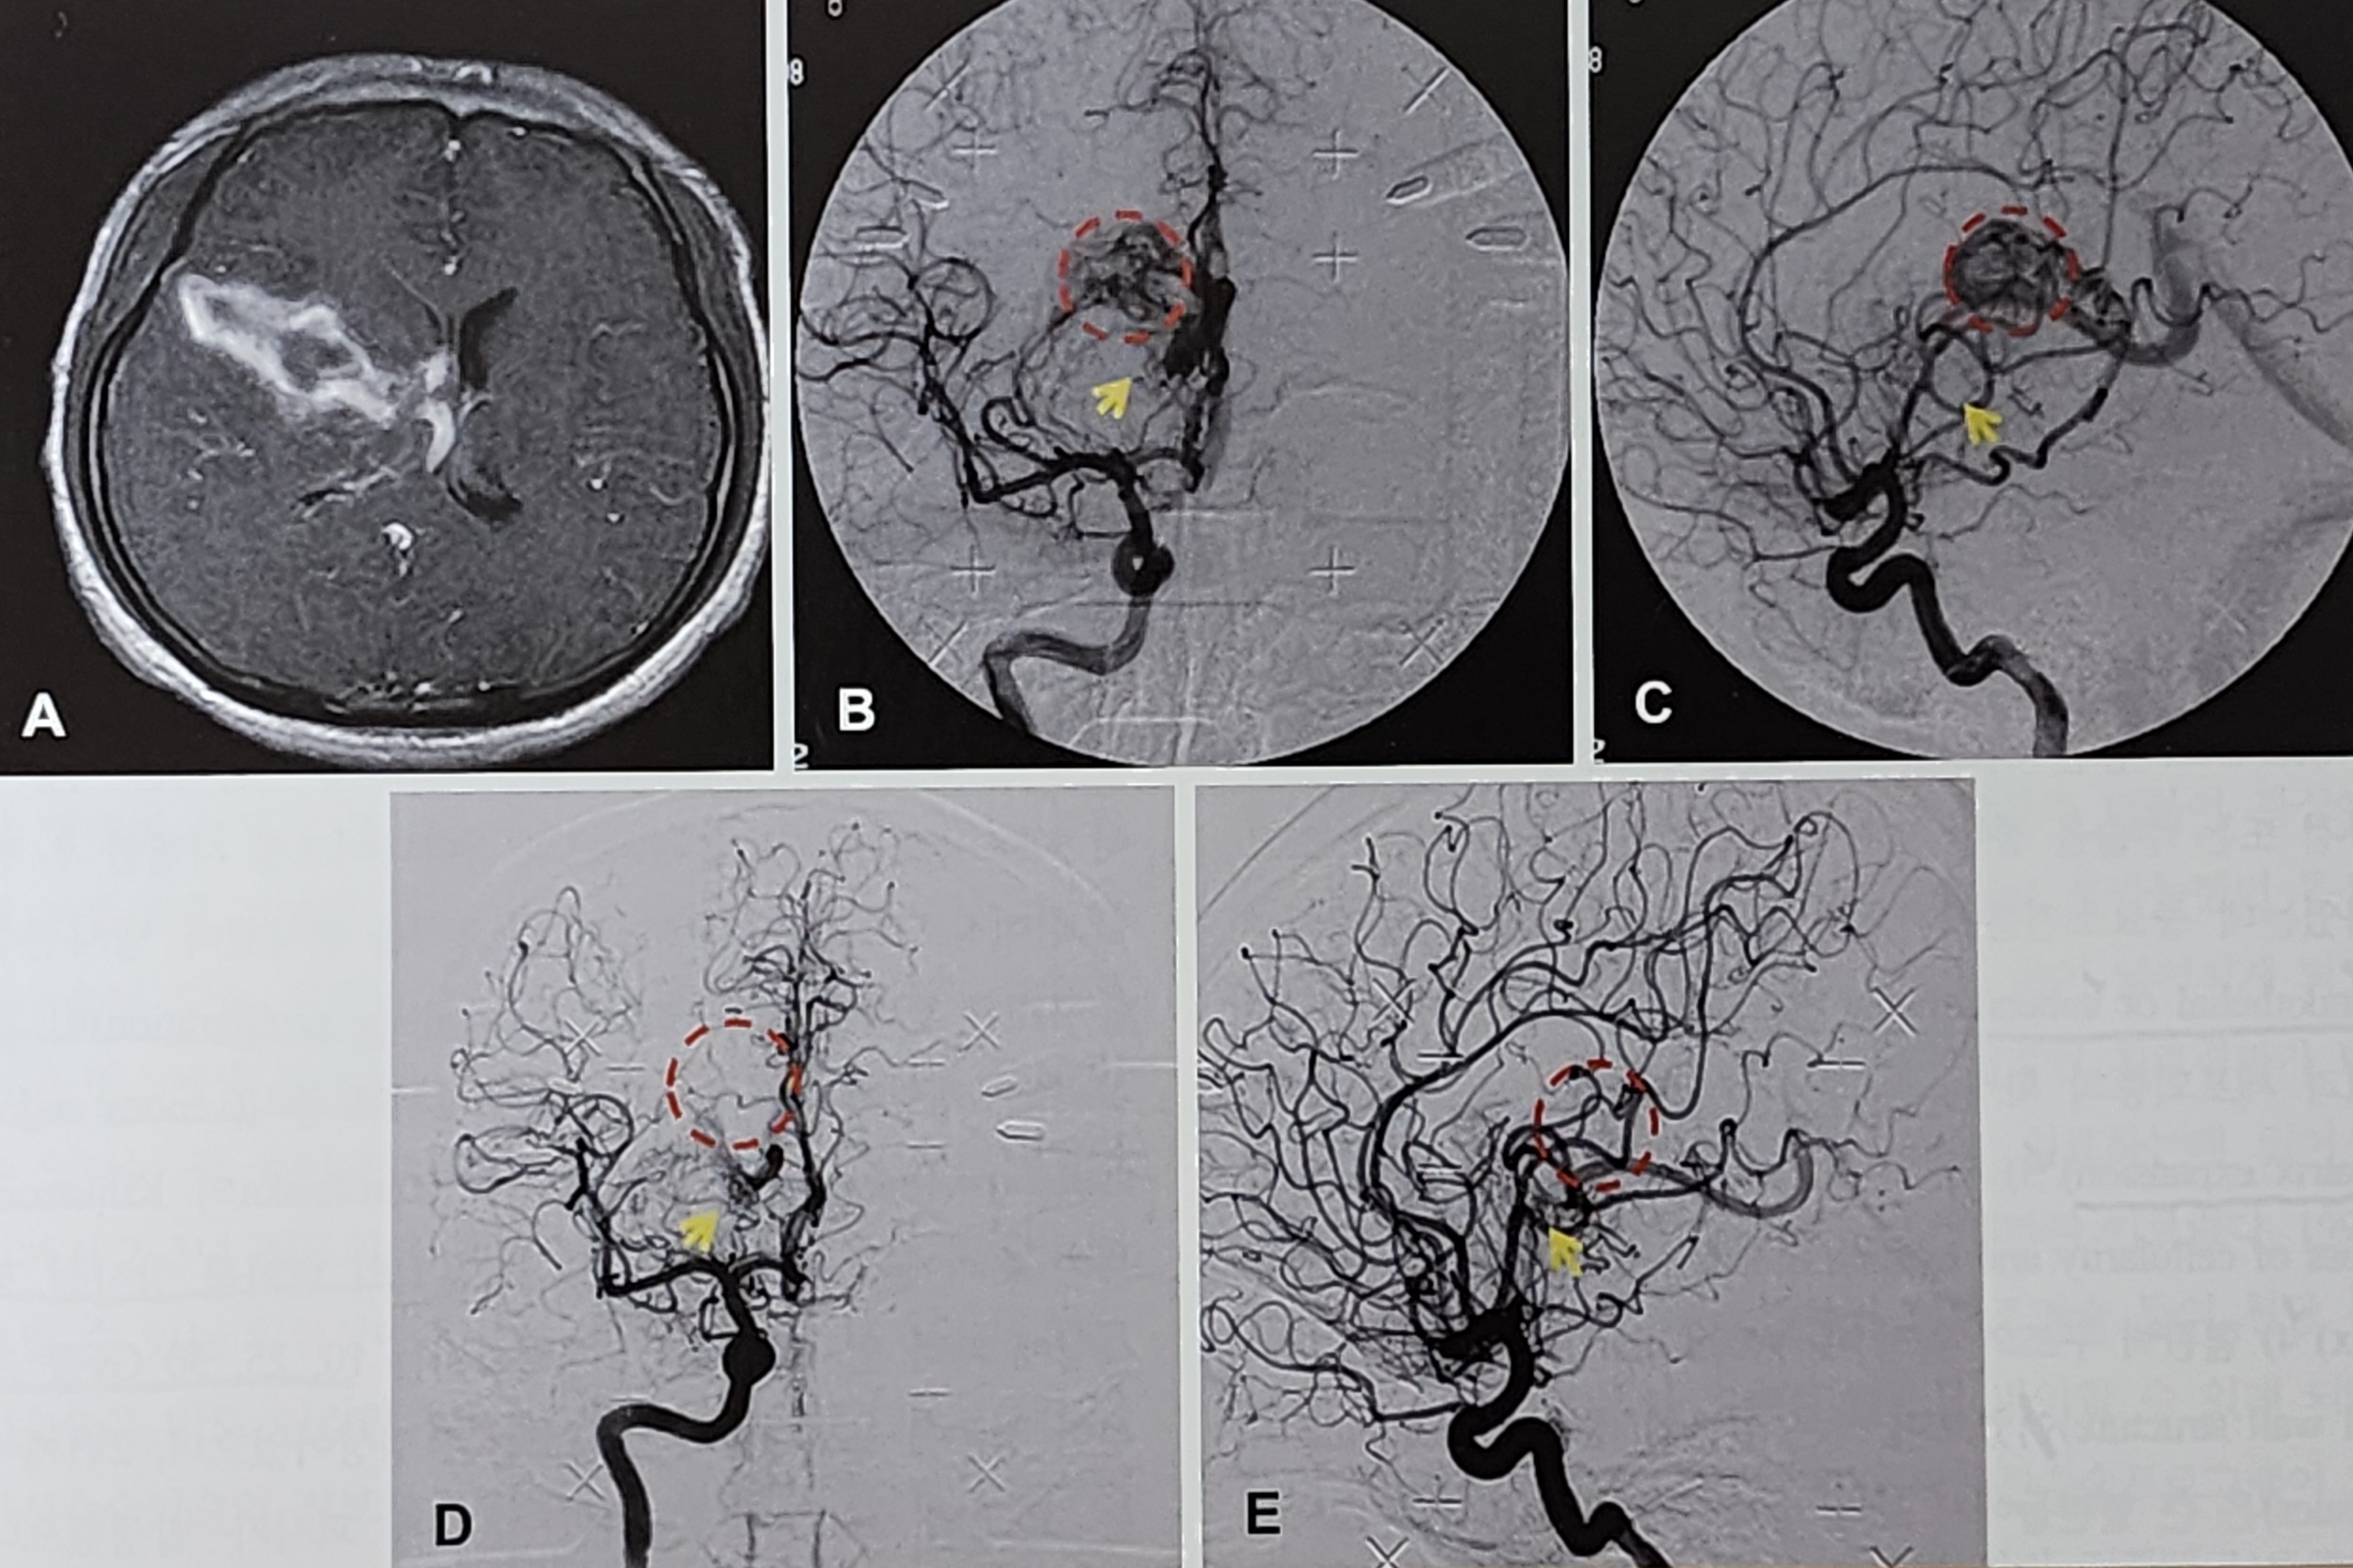

뇌혈관기형은 비정상적인 혈관 연결 구조로 인해 다양한 신경학적 증상을 유발할 수 있는 병변이다. 대표적인 형태로는 뇌동정맥기형(arteriovenous malformation, AVM), 해면상 혈관종(cavernous malformation), 정맥성 혈관종(venous angioma) 등이 있으며, 그중 AVM은 가장 치료적 접근이 필요한 형태다.

AVM은 동맥과 정맥이 모세혈관 없이 바로 연결되어 있어 고압 혈류가 흐르며, 이로 인해 뇌출혈, 경련, 두통, 신경학적 결손 등을 유발할 수 있다. 특히 AVM은 젊은 연령층에서 진단되는 경우가 많아 조기 발견과 적극적인 치료가 중요하다.

AVM에 대한 방사선수술은 병소의 크기, 위치, 형태, 환자의 나이 등 다양한 인자에 따라 치료 성과가 달라진다. 완전 폐쇄율은 보통 60%~85% 정도로 보고되고 있으며, 병소가 작고(compact), 젊은 환자이며, 병변이 반구 위치에 있고, 배출 정맥 수가 적은 경우(fewer draining vein)에서 예후가 더 좋다.

반면, 병소가 10cc 이상이거나 직경 3cm를 넘는 경우 치료 난이도가 급격히 상승하며, staged radiosurgery 또는 보조적 색전술이 필요할 수 있다.

거대 뇌동정맥기형(large-sized AVM)은 보통 10cc 이상 또는 직경 3cm 이상으로 정의되며, 단일 방사선 조사로는 완전 폐쇄가 어렵다. 이 경우 다음과 같은 전략들이 사용된다.

- 색전술과 병행: 방사선 조사 전 병소의 혈류를 감소시키는 색전술을 통해 치료 효과 향상.